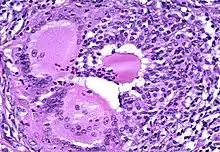

| Above shows two parts of the thyroid that could potentially be affected if diagnosed with thyroiditis. | |